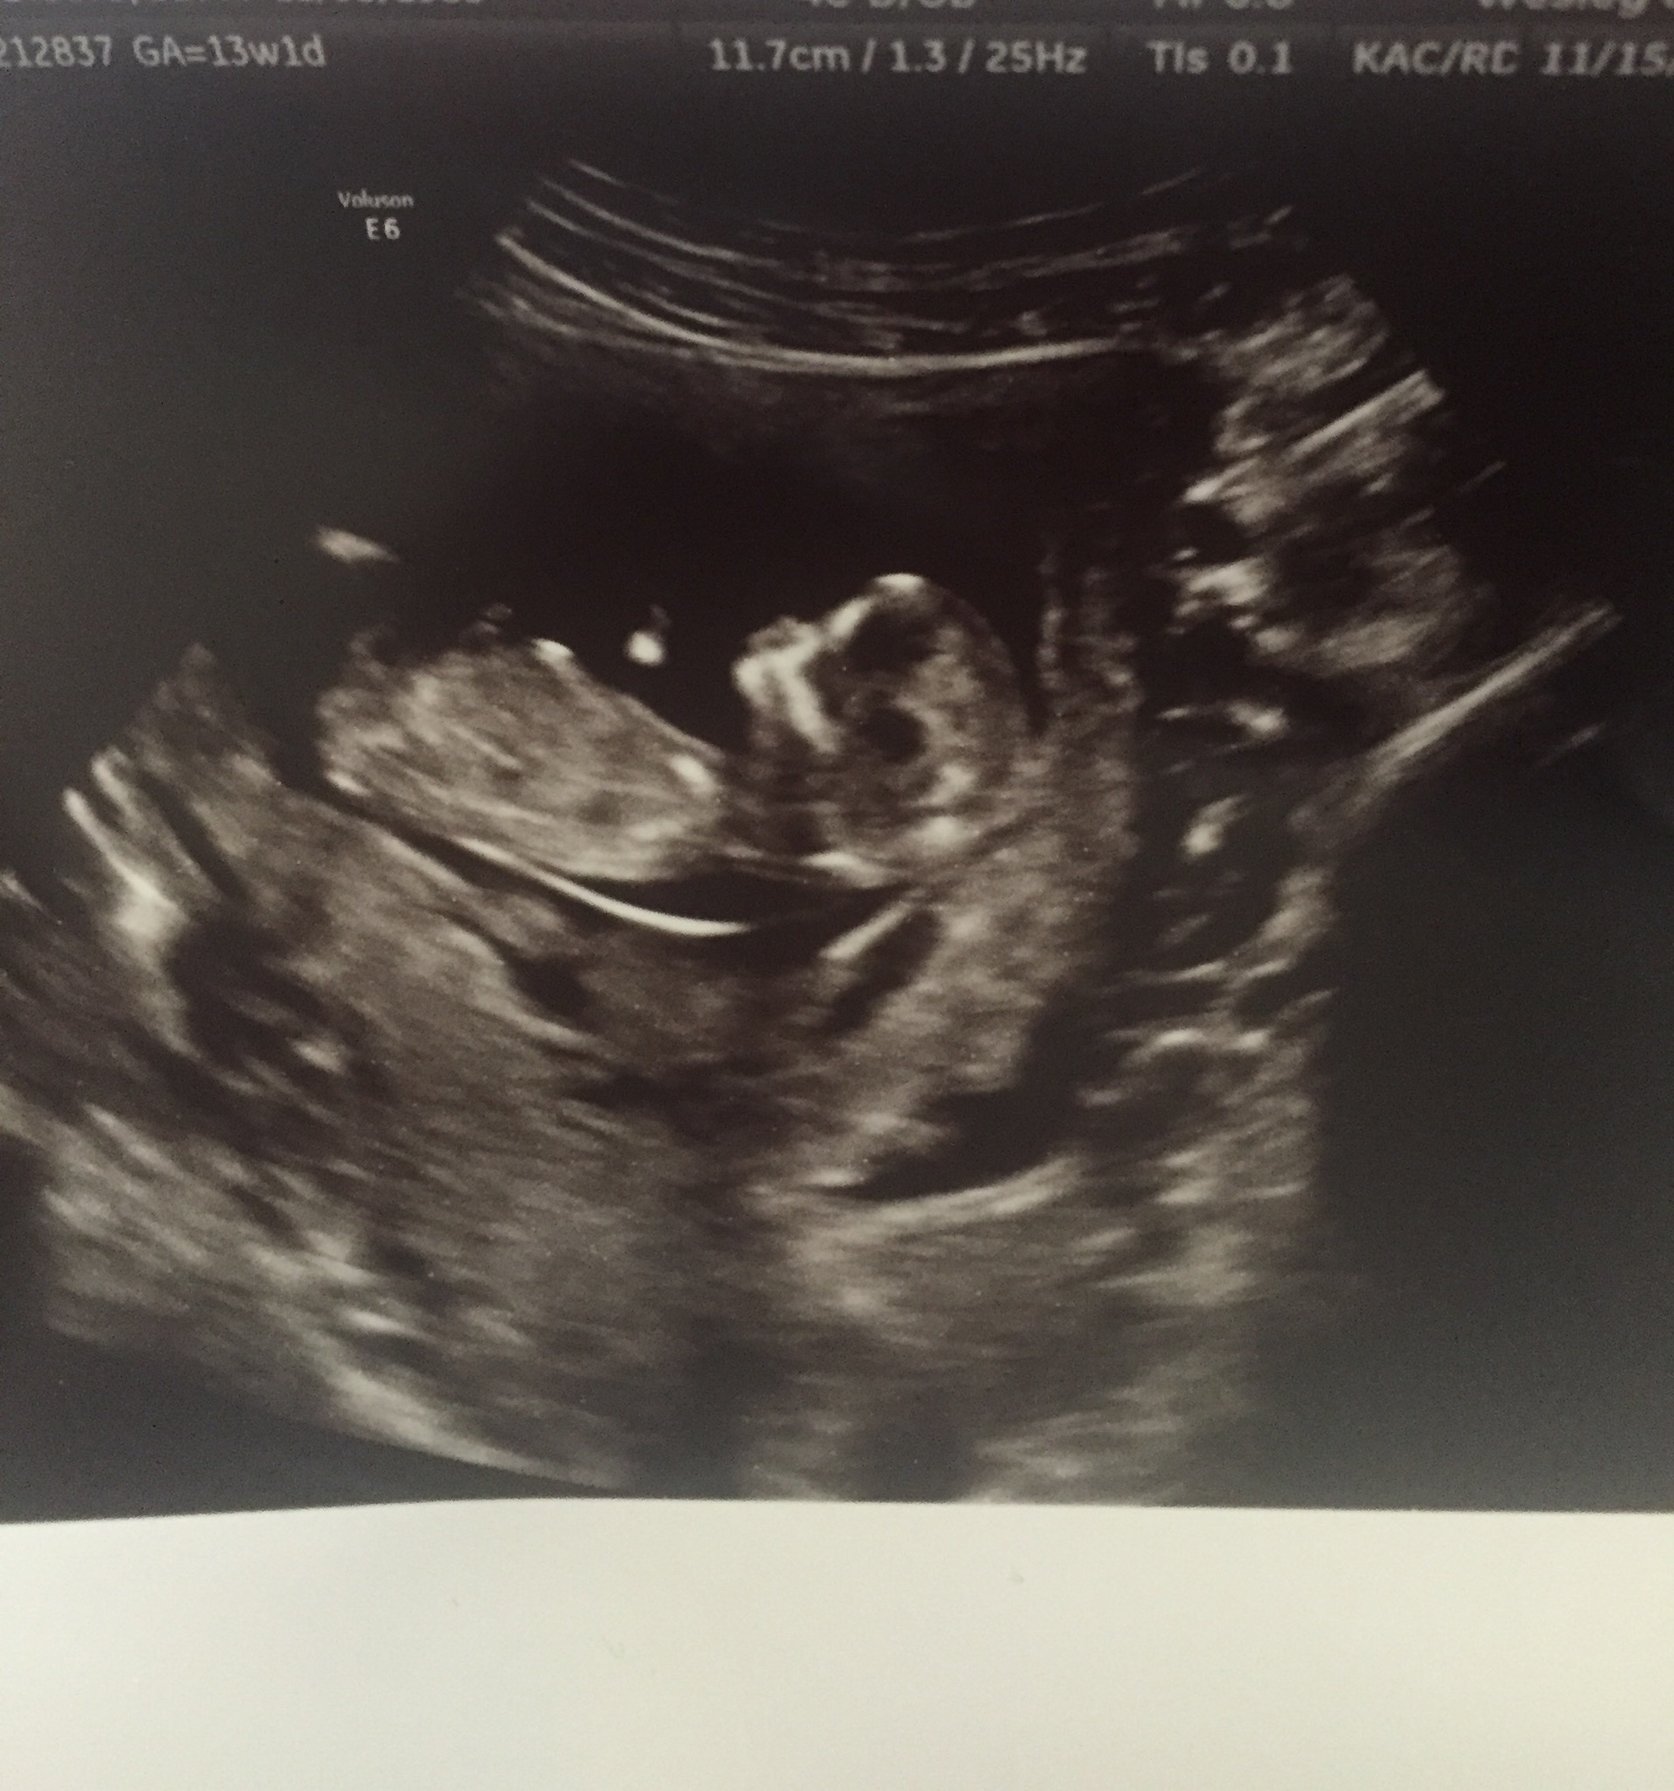

Boy or girl nub

keep in mind thighs legs n toes sticking up